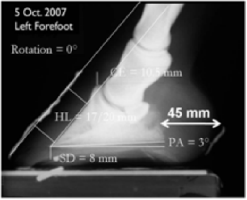

Measurements can be taken of collateral sulci depth at the back of the foot and at the apex of the frog of a live horse. These measurements have an undocumented, unproven but anecdotally consistent relationship with P3 orientation within the hoof capsule

[Fig 1- 4 pictures below] Before taking radiographs, the investigators used the CS measurements to predict 3 degree palmar angle and a 16mm sole depth

The radiograph below verified that the predictions were reasonably accurate. The accuracy of these predictions is made possible by the consistency of the externally visible collateral sulci to the third phalanx [red arrow below]